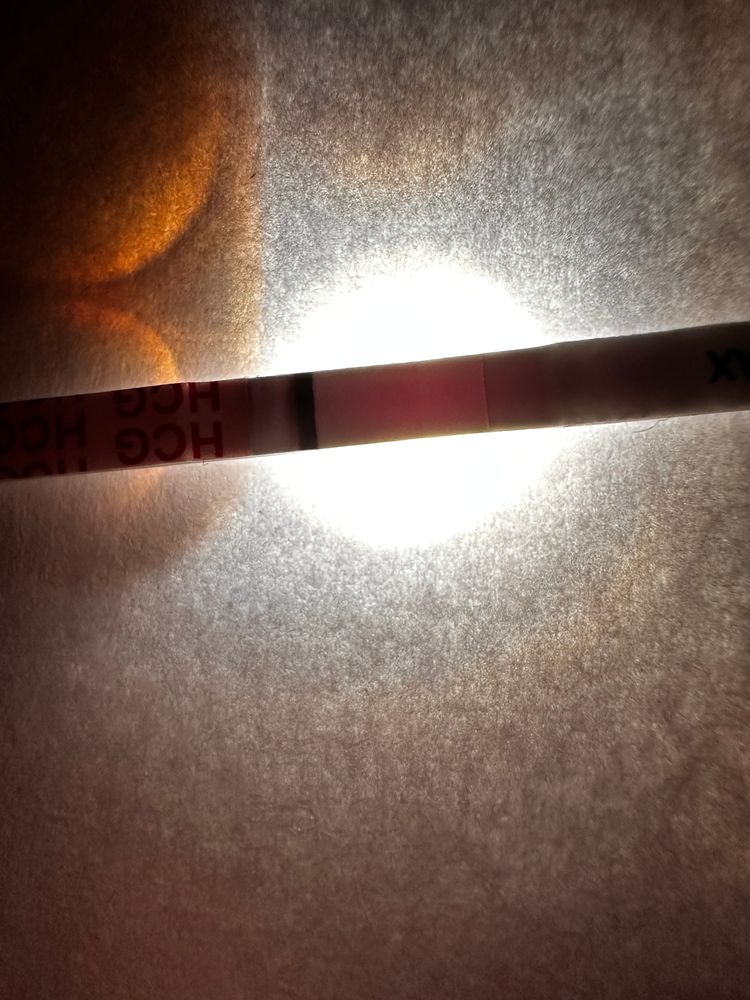

Девачки, почитала всех и короче пошла тесто манить , не могу уснуть теперь 😂😂😂😂 во что получилось напоминаю на 6 дпо

тест на о сегодняшний

Тест с верху старый 2 цикла назад

у меня в беременность именно тесты на овуляцию показали жирные // , сделала тест на б и была еле заметная полоска . Сейчас прикреплю . Но к сожалению замерла на 6 Нед

а тесты на овуляцию уменьшались после овуляции? Или тоже оставались насыщенными?

Алина Горева, прям сразу после овуляции? Такие жирные как у меня после 01.02? Или жирнее?)